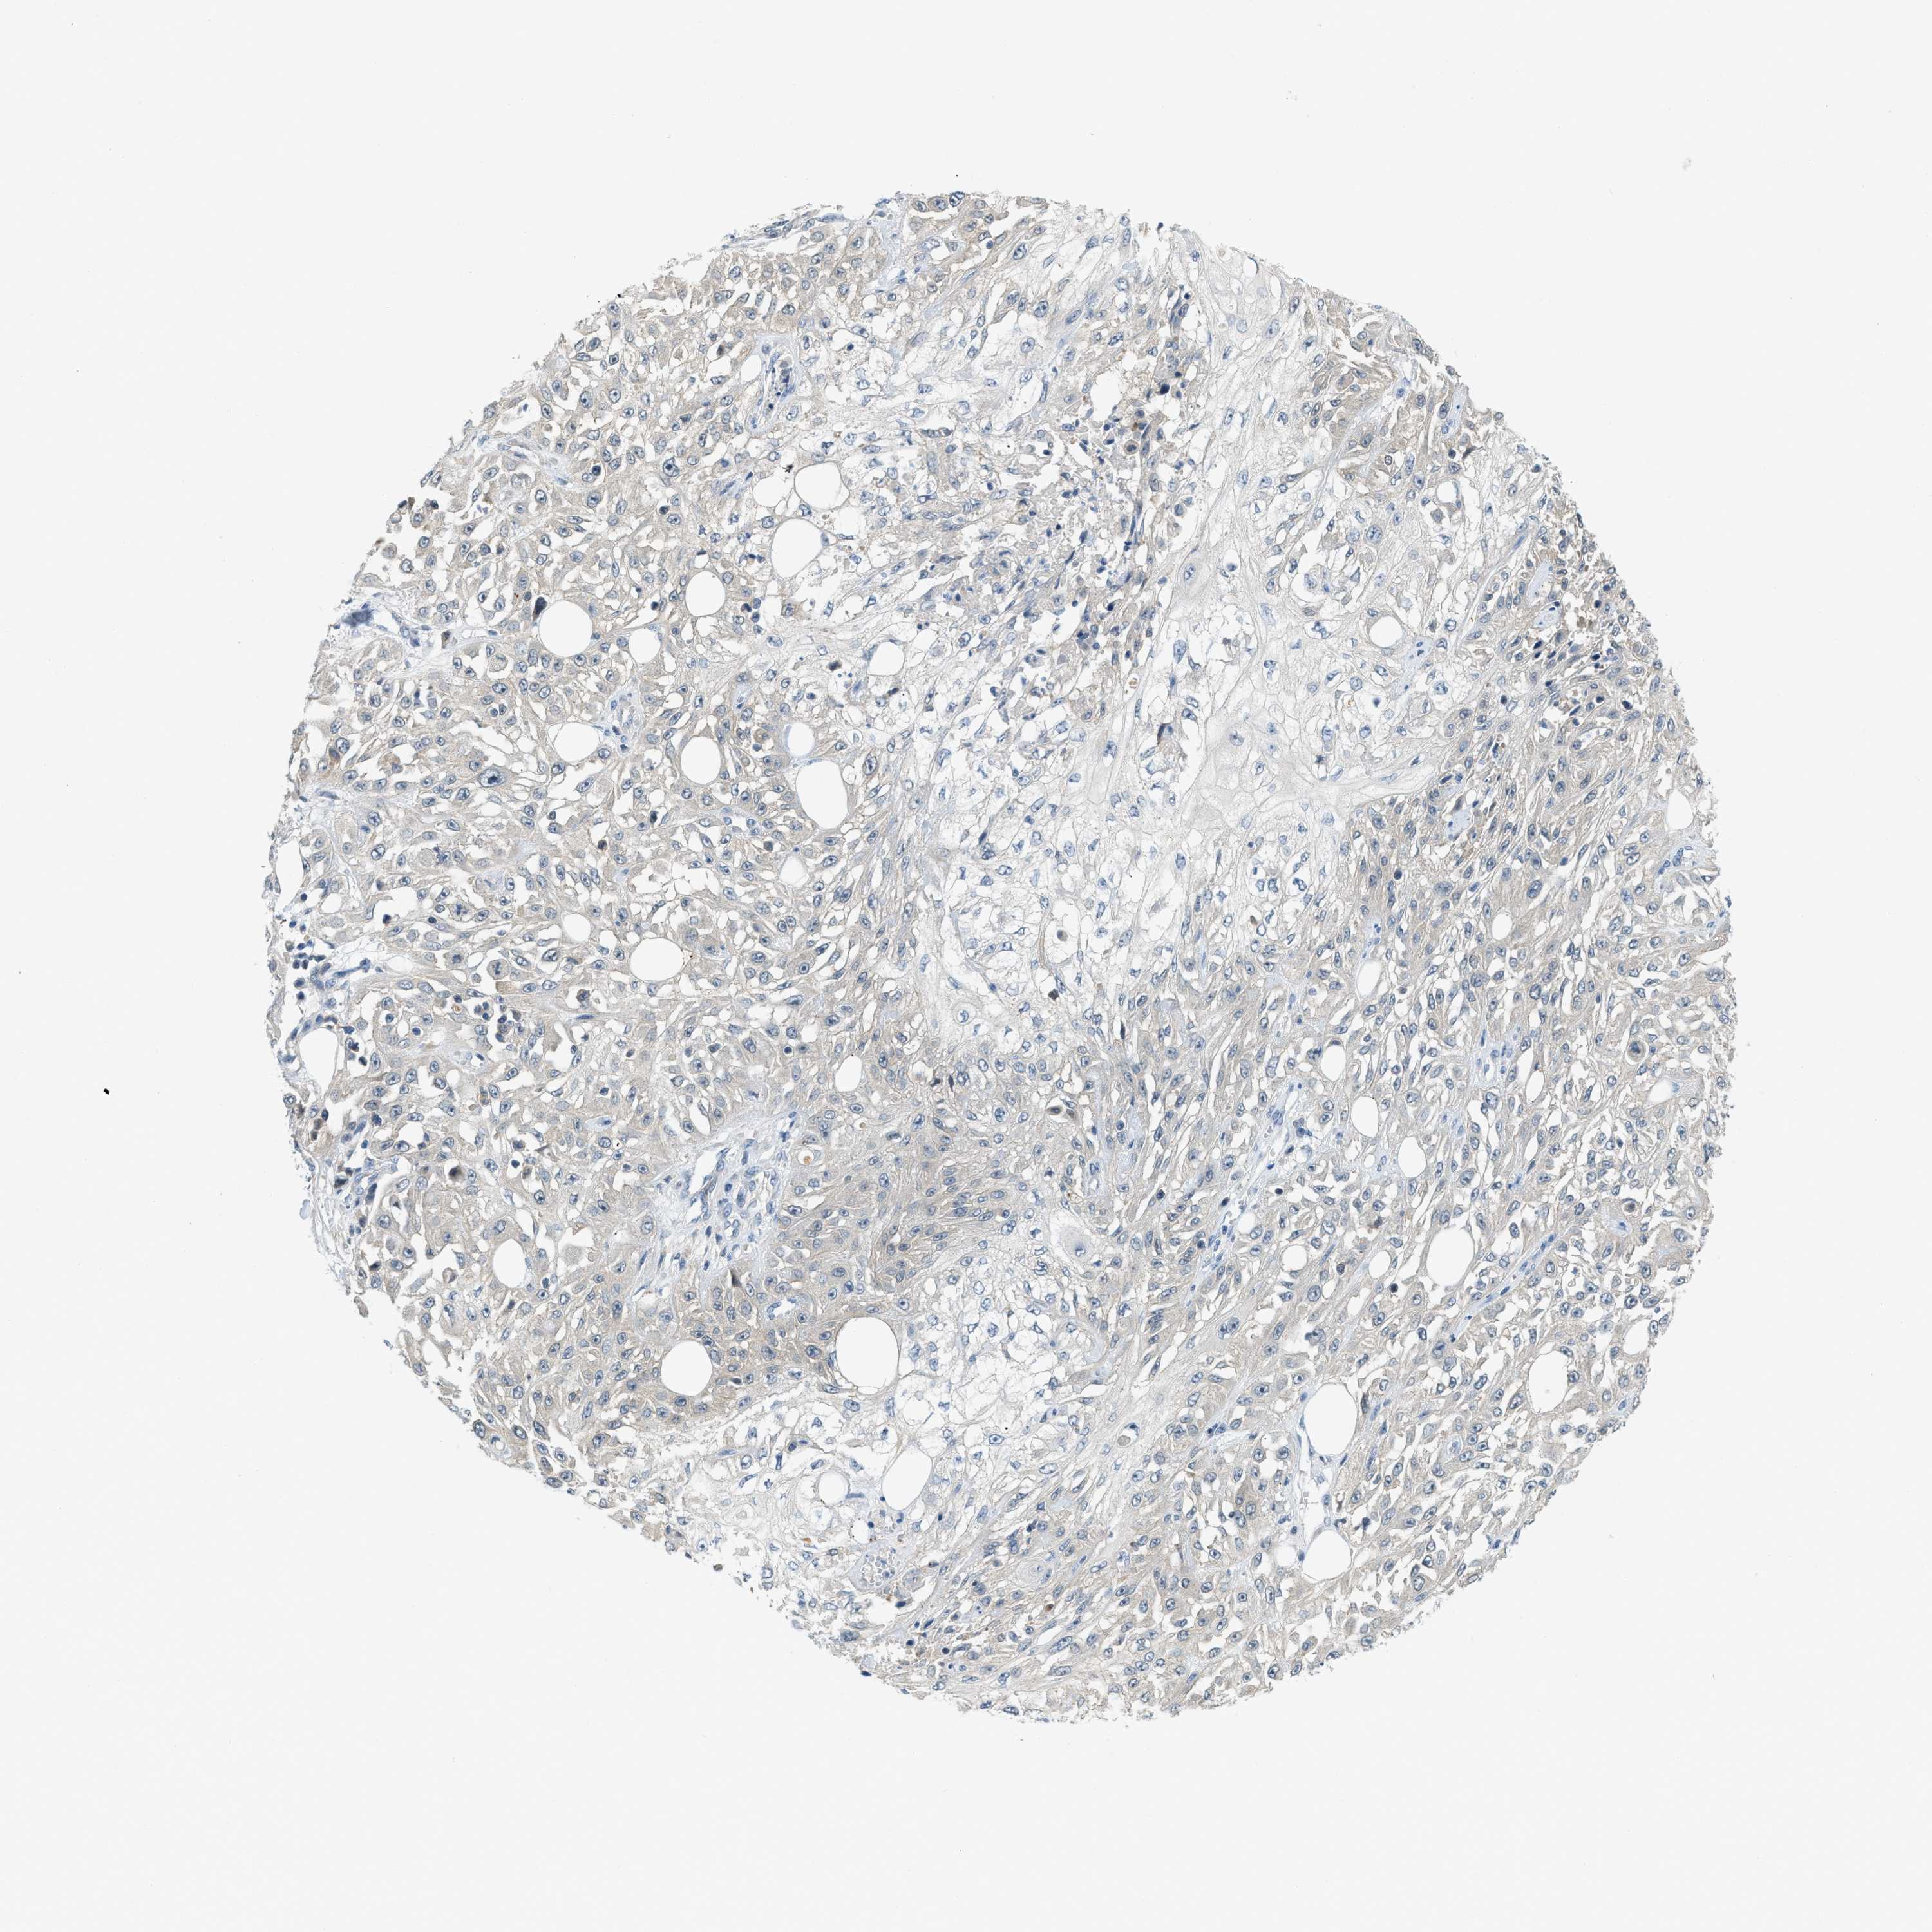

SKIN CANCER - Protein expressioni

A mouse-over function shows sample information and annotation data. Click on an image to view it in a full screen mode. Samples can be filtered based on level of antibody staining by selecting one or several of the following categories: high, medium, low and not detected. The assay and annotation is described here.

Antibody stainingi

Antibody staining in the annotated cell types in the current human tissue is reported as not detected, low, medium, or high, based on conventional immunohistochemistry profiling in selected tissues. This score is based on the combination of the staining intensity and fraction of stained cells.

Each image is clickable and will lead to virtual microscopy that enables deeper exploration of all samples and also displays staining intensity scores, fraction scores and subcellular localization as well as patient and tissue information for each sample.

Antibody HPA019259

Basal cell carcinoma